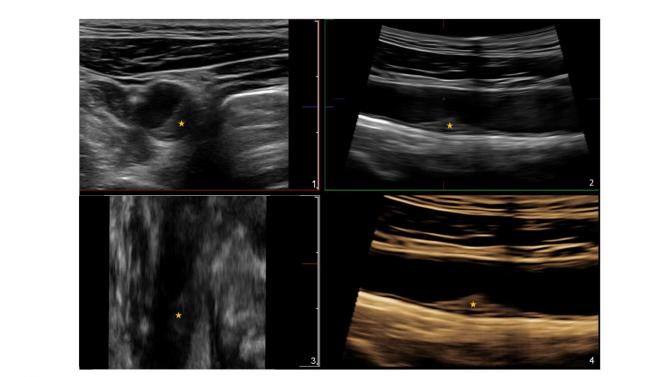

Gracias a estas técnicas de imagen, especialmente las más sencillas, accesibles y que no necesitan radiación, como la ecografía vascular 2D y 3D, explica el Borja Dr. Ibáñez, director de Investigación Clínica del CNIC, "podemos detectar y cuantificar la carga o el volumen de enfermedad aterosclerótica y monitorizarla de una forma precisa para así identificar a aquellos individuos que se puedan beneficiar potencialmente de una prevención más intensiva de forma precoz".

Las recientes Guías de Prevención Europeas 2019 reconocen la utilidad de la evaluación de la aterosclerosis con técnicas de imagen para evaluar el riesgo en los individuos más allá de los factores de riesgo convencionales -edad, sexo, hipertensión, colesterol, tabaco y diabetes-. "La técnica recomendada es el TAC de baja dosis de radiación, que evalúa la presencia de calcio en las arterias coronarias como dato indirecto de la presencia de placas de aterosclerosis. Pero, además, -indica el Dr. Ibáñez-, las Guías también ponen en valor la utilidad de la evaluación de la carga de aterosclerosis carotidea y femoral mediante la ecografía".

Lo que ahora aporta el estudio que se publica en JACC es un seguimiento a 3 años del estudio PESA en el que se ha llevado a cabo la primera comparación directa entre ambos marcadores de riesgo en imagen, el calcio coronario por TAC y la carga de aterosclerosis carotidea y femoral por ecografía 2D/3D. Y los resultados, destaca la Dra. Beatriz López-Melgar, autora principal del artículo, "muestran que la ecografía de las arterias periféricas es capaz de detectar la progresión de la aterosclerosis de una forma más eficiente que el estudio del calcio coronario por TAC".